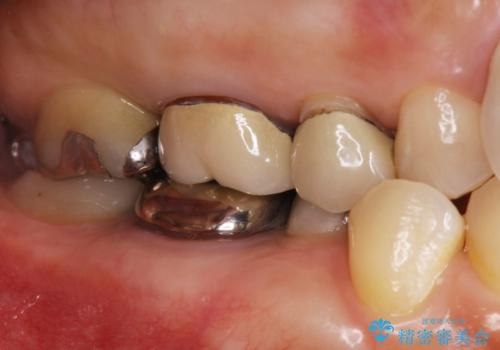

- 右上の奥歯がしみるとのことで確認すると、右上の一番奥の歯の銀歯の下が虫歯になっていました。

かなり大きな銀歯が装着されていたので、かぶせ物にて治療を行うこととなりました。

同時に右上の後ろから3番目の歯のかぶせ物も適合が悪かったので同時に治療することとなりました。